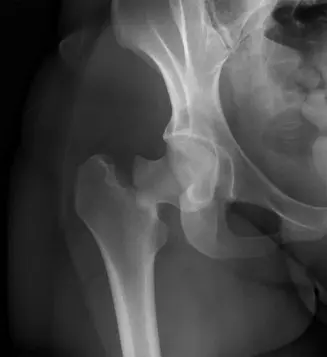

الأشعة السينية (Plain Radiographs)

يتم الحصول على صور بالأشعة السينية للحوض بالمنظر الأمامي الخلفي (AP Pelvis) وصورة جانبية مخصصة للورك المصاب (Cross-table Lateral Hip).

- صورة الحوض الأمامية الخلفية (AP Pelvis): أظهرت كسرًا داخل المحفظة المفصلية لعنق الفخذ الأيمن مع إزاحة. كان خط الكسر مائلًا، ويمتد من المنطقة تحت الرأسية إلى الأسفل والوسط. كان رأس الفخذ في وضعية إزاحة للخارج (valgus) بالنسبة لجذع الفخذ، وكان هناك حوالي 1 سم من الإزاحة العلوية لجذع الفخذ بالنسبة للرأس. بدا المدور الكبير سليمًا.

- صورة الورك الجانبية (Cross-table Lateral Hip): أكدت الإزاحة وقدمت رؤية أوضح لشكل الكسر، مبينة وجود تفتت خلفي كبير وامتداد للكسر إلى منطقة قاعدة العنق (basicervical region).

توضح هذه الصورة كسرًا في عنق الفخذ من النوع الثالث حسب تصنيف جاردن، مع انحشار وإزاحة للخارج.

تصنيف جاردن (Garden Classification): يعتمد على درجة الإزاحة الظاهرة في صورة الأشعة السينية الأمامية الخلفية.

- النوع الأول (Garden Type I): كسر غير كامل أو منضغط مع إزاحة خارجية (valgus impaction)، مستقر نسبيًا.

- النوع الثاني (Garden Type II): كسر كامل ولكن بدون إزاحة.

- النوع الثالث (Garden Type III): كسر كامل مع إزاحة جزئية وانحشار خارجي (valgus displacement and impaction)، ولكن لا يزال هناك بعض الاتصال بين العظمين. هذا هو النوع الذي وصف في دراسة الحالة.

- النوع الرابع (Garden Type IV): كسر كامل مع إزاحة كاملة وفقدان تام للاتصال بين العظمين، وغالبًا ما يكون هناك إزاحة داخلية (varus displacement).